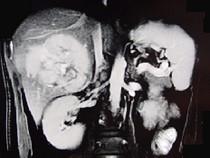

问题 男,36岁,腹胀、消化不良、消瘦、中上腹痛,影像检查如下图,最可能的诊断是()

选项 A.胃间质肉瘤并肝转移 B.胃间质瘤并原发性肝癌 C.内胚窦瘤肝转移 D.胃淋巴瘤伴原发性肝癌 E.胃间质瘤并肝血管瘤

答案 A